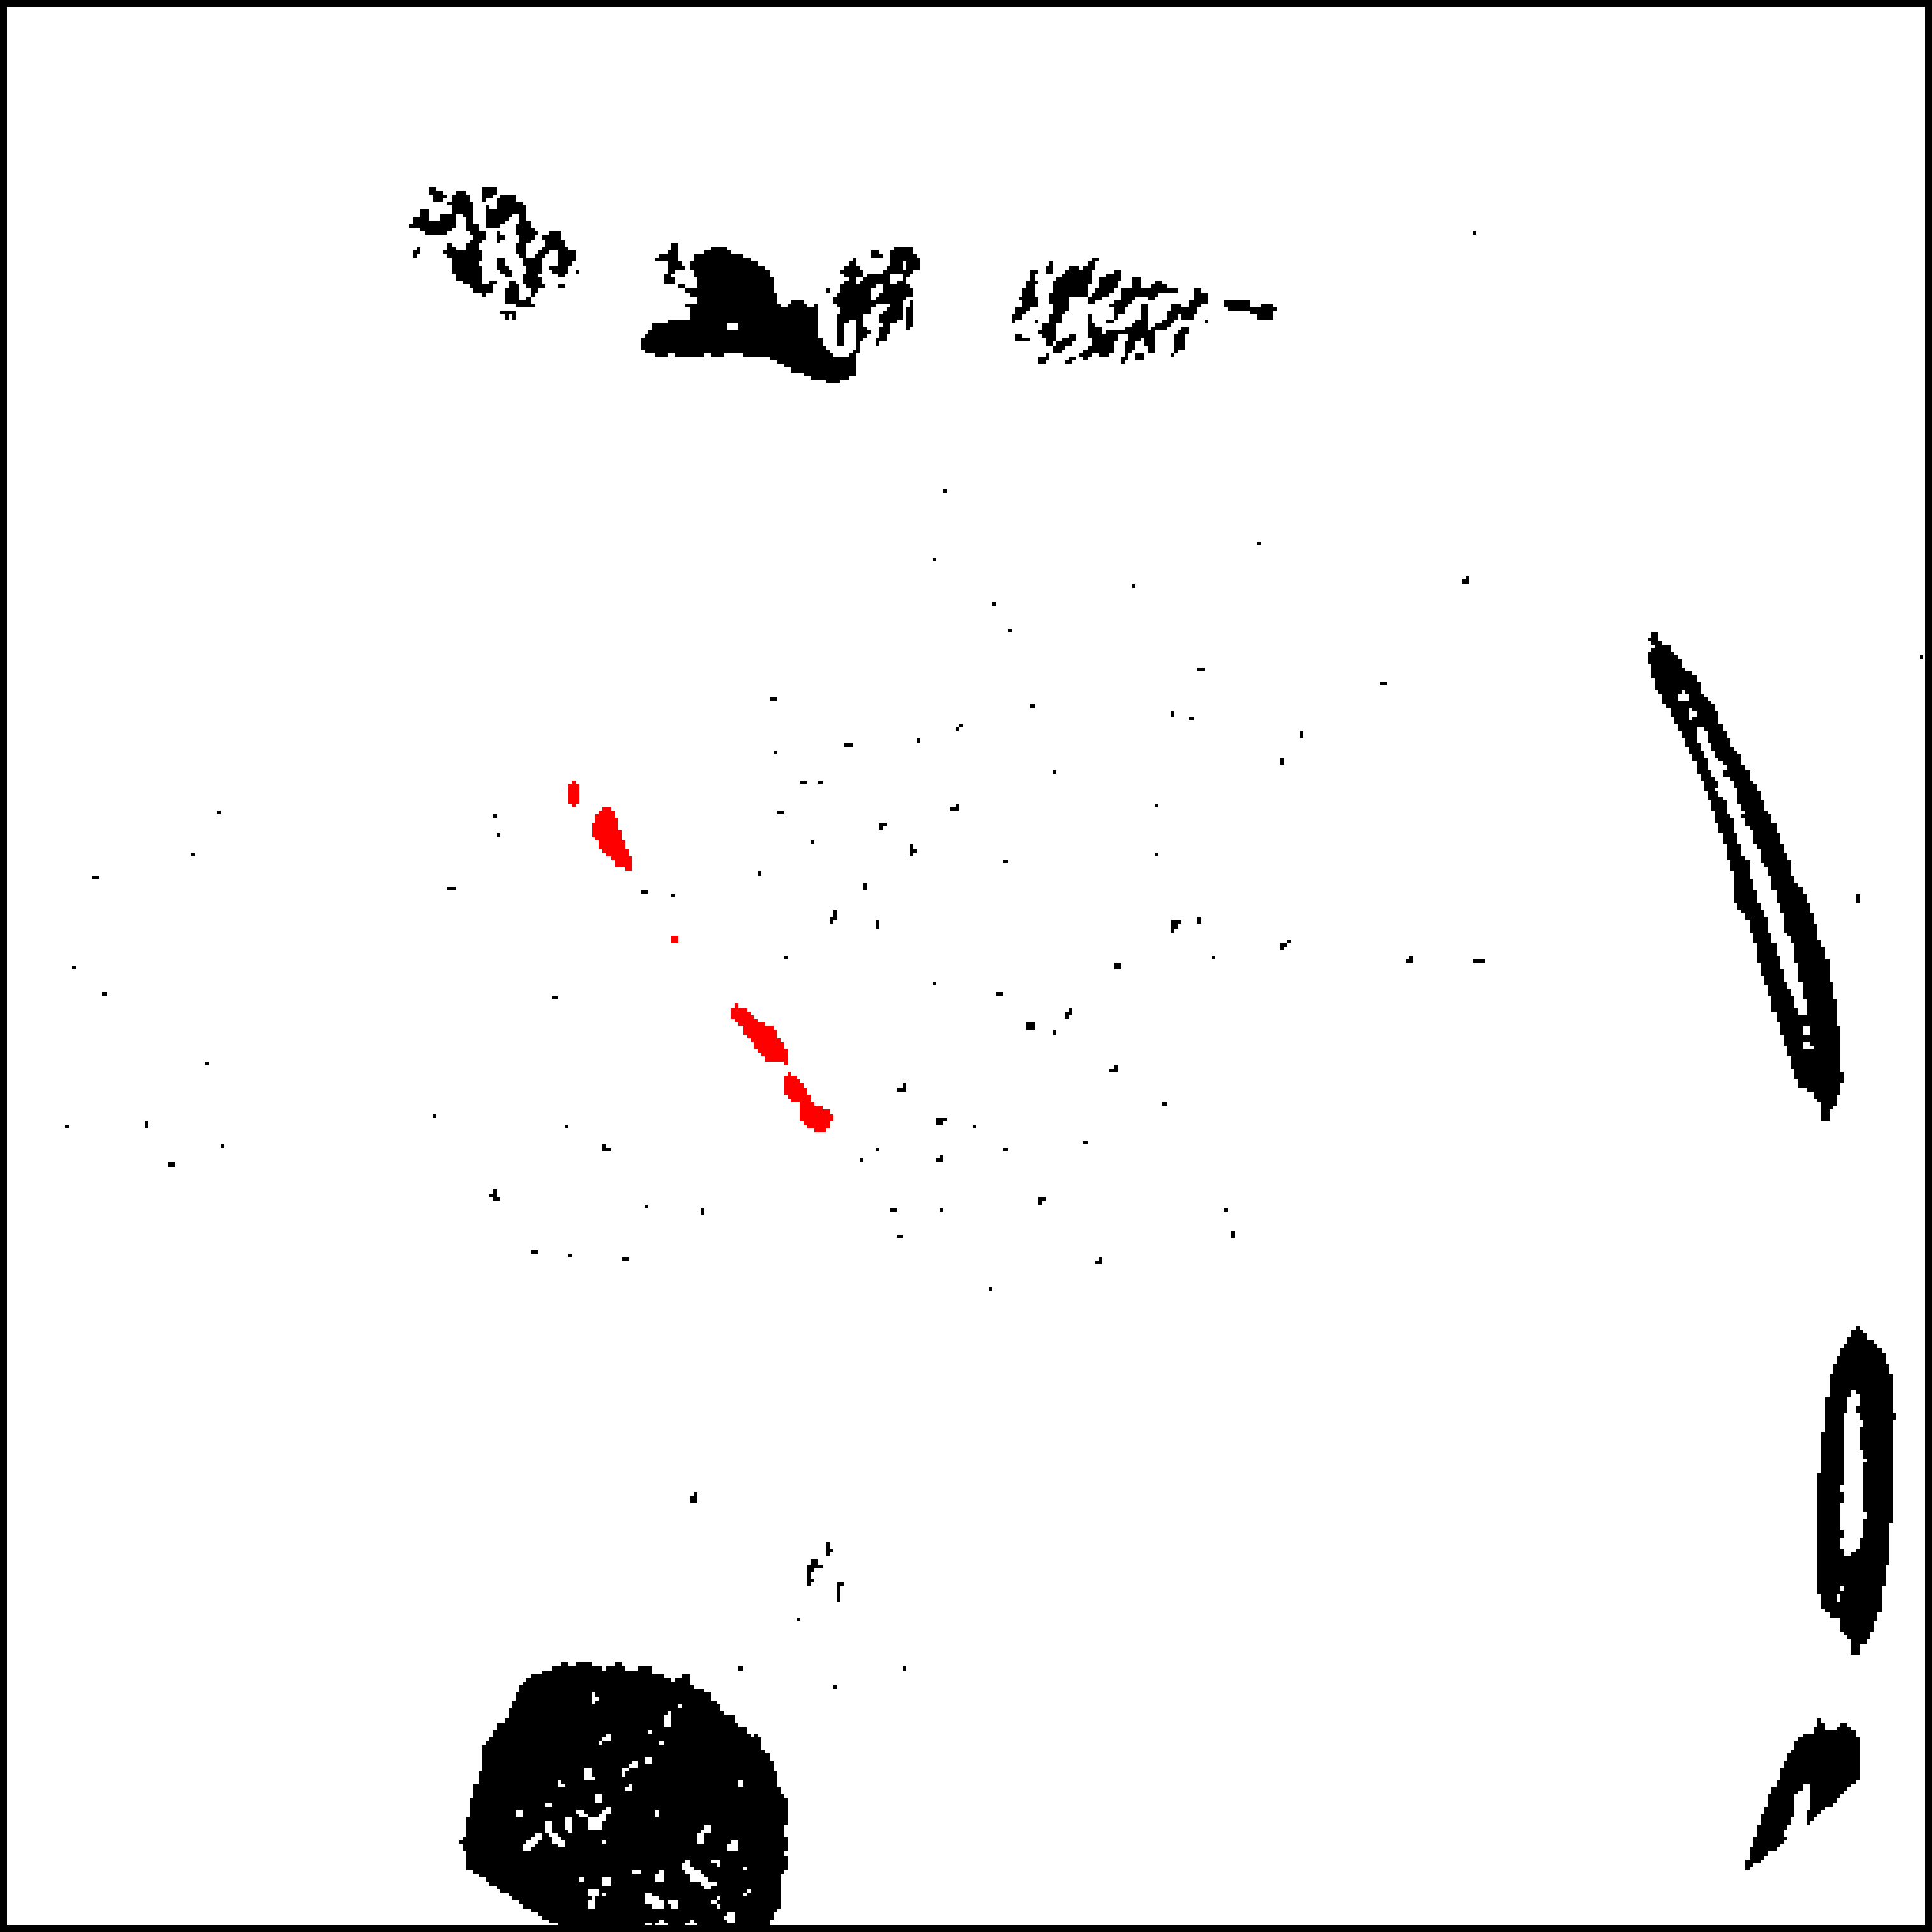

The theory and framework for domain adaptation via adversarial training presented in Sec. 4 has formed the basis for several works in biomedical image analysis. Kamnitsas et al. [52] proposed employing domain adversarial networks for alleviating problematic segmentation due to domain shift between MR acquisition protocols. Extending the basic framework, they proposed multi-connected adversarial nets, which enable the domain discriminator to process information from several layers of the feature extractor (Fig. 10). Empirical analysis showed that this leads to a higher quality domain classifier, hence flow of better gradients to the primary network and improved adaptation. By applying the technique to adapt between two databases of multi-modal MR brain scans with traumatic brain lesions, where one of the modalities differed (Fig. 11), they showed that domain adversarial training is applicable to 3D CNNs for volumetric image processing. This was previously questioned in the literature [53] due to memory constraints.

Refer to caption

Figure 11: Result from Kamnitsas et al [52]. A CNN for segmentation of brain lesions is trained on a database of multi-modal MR scans, which include gradient echo (GE) sequence. The CNN fails when it is applied on another study, where susceptibility weighted imaging was acquired instead of GE. Domain adaptation alleviates the issue.